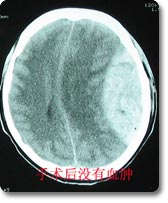

神经外科治疗各种颅脑损伤病人已有50余年历史,拥有一支高素质的专业医护队伍,先后收治各类颅脑损伤病人7000余例,尤其是在严重颅脑损伤的抢救方面,已总结出一整套抢救治疗方案,积累了丰富的救治经验,救治成功率高于文献报导的平均水平,死亡率、残废率低。 |